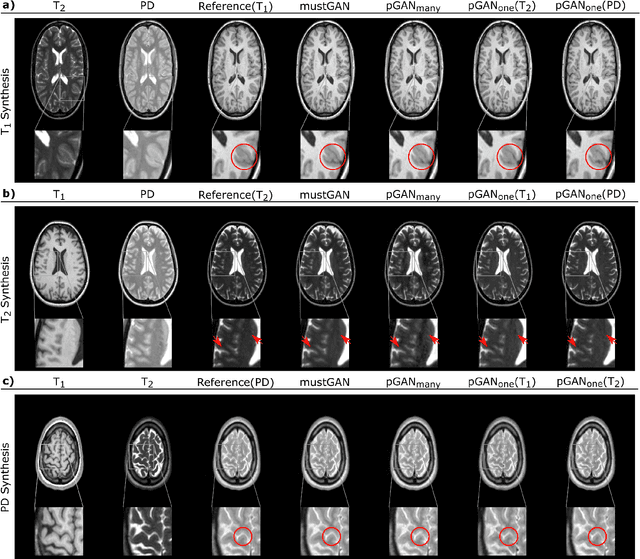

Abstract:Multi-contrast MRI protocols increase the level of morphological information available for diagnosis. Yet, the number and quality of contrasts is limited in practice by various factors including scan time and patient motion. Synthesis of missing or corrupted contrasts can alleviate this limitation to improve clinical utility. Common approaches for multi-contrast MRI involve either one-to-one and many-to-one synthesis methods. One-to-one methods take as input a single source contrast, and they learn a latent representation sensitive to unique features of the source. Meanwhile, many-to-one methods receive multiple distinct sources, and they learn a shared latent representation more sensitive to common features across sources. For enhanced image synthesis, here we propose a multi-stream approach that aggregates information across multiple source images via a mixture of multiple one-to-one streams and a joint many-to-one stream. The shared feature maps generated in the many-to-one stream and the complementary feature maps generated in the one-to-one streams are combined with a fusion block. The location of the fusion block is adaptively modified to maximize task-specific performance. Qualitative and quantitative assessments on T1-, T2-, PD-weighted and FLAIR images clearly demonstrate the superior performance of the proposed method compared to previous state-of-the-art one-to-one and many-to-one methods.